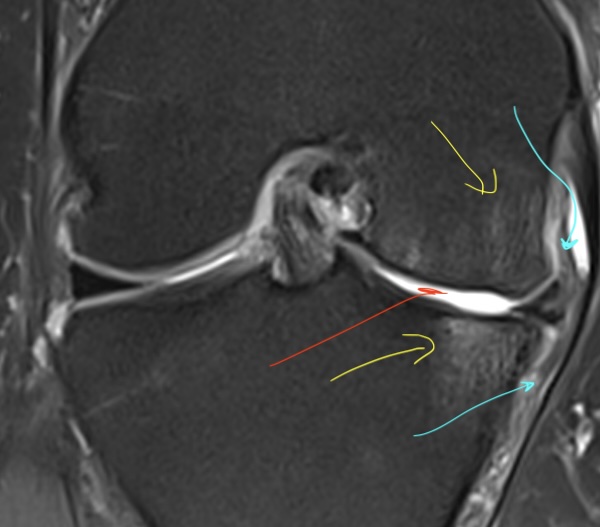

Qu'est-ce que la chondropathie ?

L'usure commence doucement par de petites lésions superficielles du cartilage, appelées chondropathies. Leur diagnostic se fait sur une IRM ou un arthroscanner.

Quand les lésions progressent, les os se retrouvent en contact direct, ce qui rend les mouvements articulaires difficiles et douloureux.